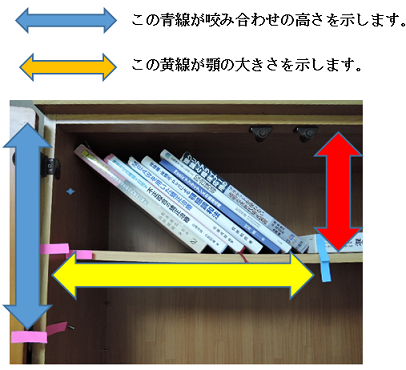

MEAW(マルチループ)を利用して歯を動かす隙間の作り方は2種類あります。

②ふたつ目は以下の様な原理です。

①では歯が近心側に綺麗に傾いた場合ですが、歯が内側(舌側)に傾く事もあります。

この場合もMEAW(マルチループ)によって内側(舌側)に傾むいた歯を起こしていきます。

MEAW(マルチループ)を利用して歯を動かす隙間の作り方は2種類あります。

①ひとつ目は以下の様な原理です。

これを身近な7冊の本を使って説明していきましょう。